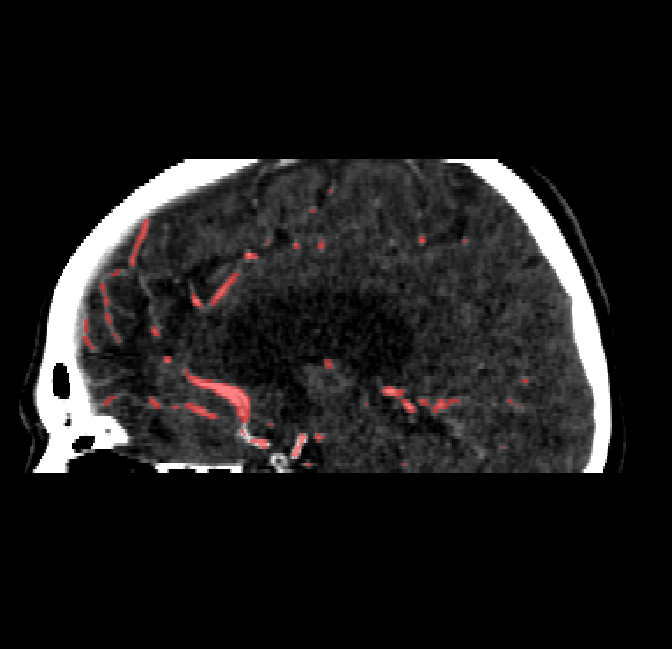

Qualitative Results

After fine-tuning, the two pre-train conditions appear to have little or no difference in terms of qualitative performance at the vessel segmentation task. However, when compared to the models trained only on real data, there are noticeable differences. Throughout Figures 4.3-4.9, the model pre-trained on scans with original CT noise is to be taken as representative of segmentation performed by the Perlin noise pre-training condition. Images showing the hand-labeled ground truth, as well as the unlabeled slice, are presented for comparison.

Refer to caption

Figure 4.8: Side view of segmentations on regions near the left side of the skull. Unaltered image (left). No pretrain model (mid-left). Fine-tuned model (mid-right). Hand-labeled ground truth (right).

For vessels in the center of the head, all model types appear to accurately segment vessels. In certain cases, the models appear to learn to correctly avoid segmenting pieces of bone that could, in terms of shape and contrast, easily be confused with large vessels. An example of this can be seen in the frontal section of Figure 4.6.

The models appear to have a hard time segmenting vessels close to the skull surface. The model trained exclusively on patient data appears to struggle far more for these types on conditions than the fine-tuned models. Figure 4.8 shows an example of the fine-tuneds model having close to no trouble segmenting vessels near the left side of the skull, while the baseline model suffers heavily from false negatives. To lesser degree, this effect can also be observed in the frontal lobe of Figure 4.9 In the other hand, Figure 4.7 presents an example of both models failing to segment vessels near the top of the skull.

In the other hand, it should be noted that fine-tuned models suffered from false positives more often than models with no pre-training. The fine-tuned models appeared to occasionally segment regions near the skull, which although similar in intensity to vessels, had no resemblance in terms of shape. Examples of this are seen in Figure 4.4 near the occipital bone and near the right temporal bone. Examples of oversegmentation were observed to happen commonly around the internal carotid arteries. This is likely due to the amount of contact surface between the artery and the surrounding bone. There was also a tendency for all model conditions to segment bone regions that were similar in shape to large vessels (Figures 4.3 and 4.4). Bone structures in such regions have similar pixel intensities to the arteries transporting contrast material, which could explain the source of confusion for a model.

To our surprise, the models were able to occasionlly segment the shape of the internal carotid arteries correctly despite no boundary being visible to the naked eye between the vessel wall and the surrounding bone structure. An example of this can be seen in the fine-tuned model in Figure 4.3.